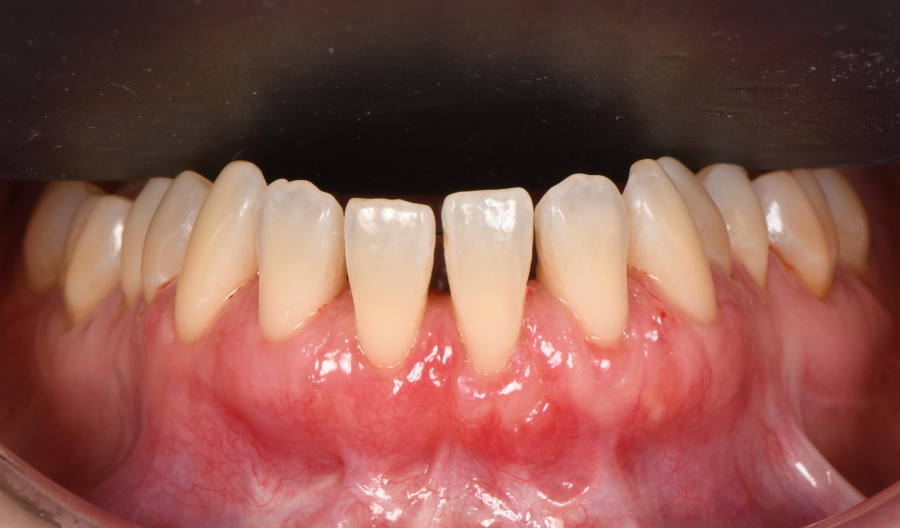

Greffe gingivale sur les 4 incisives mandibulaires